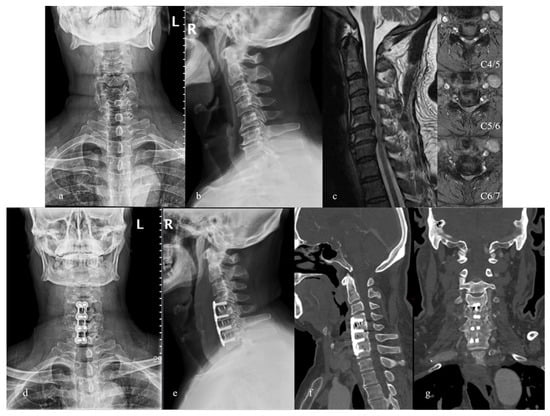

2. Materials and Methods

3. Results